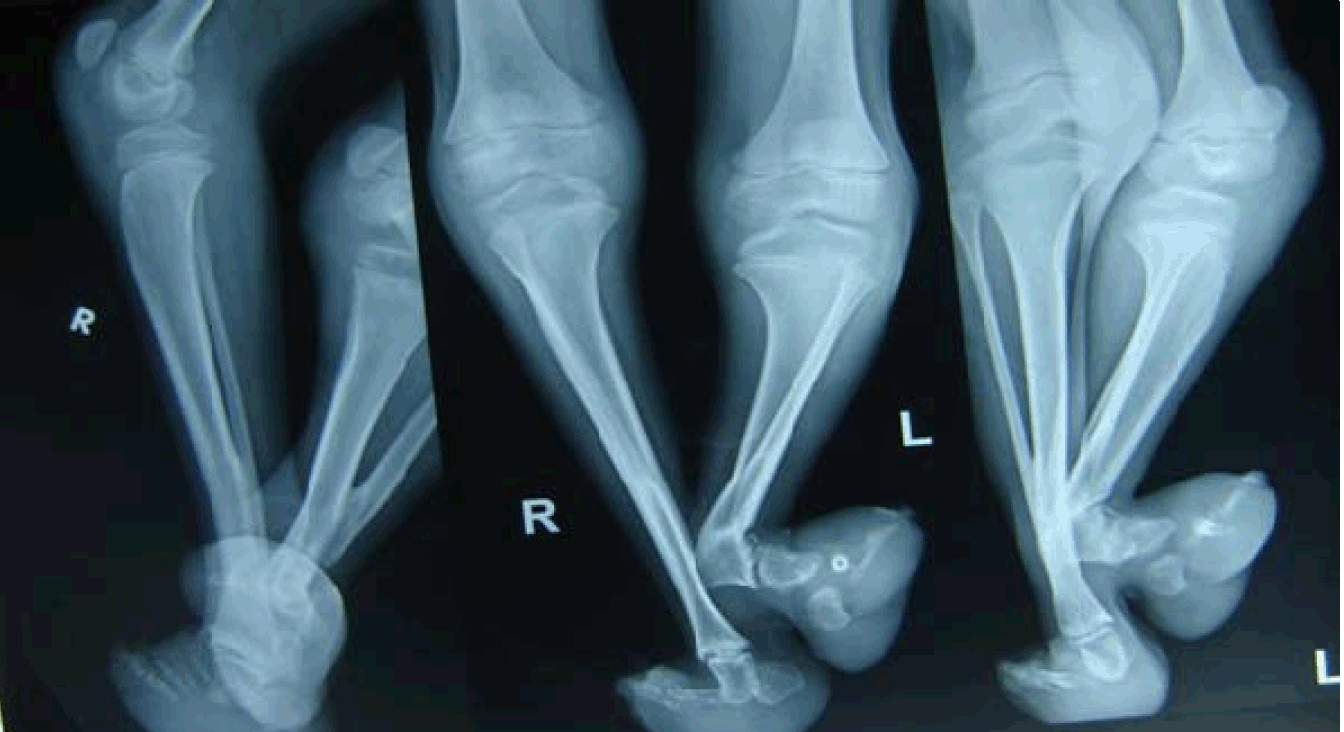

A 15-year-old boy presented to our outpatient department with deformity of both lower limbs with partial fusion of lower legs since birth. He was accompanied by his parents. On taking detailed history, it was found that parents had not ever consulted any doctor. Patient was able to ambulate independently with a single stick. He was not having any other complaint as such and was mentally normal. He was having no other physical anomalies in the skull, facies, chest and lumbar region. On examination of both the lower limbs, it was seen that pelvis and both femur were normal. The left popliteal fossa was at a lower level than the right. Fusion of the lower limbs was noted at the level of distal one-third of the leg about 8 cm above bilateral ankle joint. Below the level of fusion the right distal leg was straight but the left distal leg and ankle foot complex was deviated laterally with acute angulation. Both feet were maldeveloped with rockerbottom deformity with the absence of great toe on the left foot and few other phalanges in both feet (Figure 1) and (Figure 2). On palpation, it was felt that the proximal part of the left tibia was fused with the right tibia. X-rays confirmed our findings of fusion of bilateral tibia with acute angulation of the left tibia with partial absence of metatarsals and phalanges (Figure 3). The development of feet above the level of fusion was adequate but below this level both feet were maldeveloped. A provisional diagnosis of sirenomelia was made and further workup and plan for surgery was made. The parents agreed for workup and left to come prepared for admission but they did not come for admission and also did not respond to repeated calls.

Figure 3: X-ray features of both lower limbs showing fusion of distal part of left tibia with the right with lateral bending of left leg.